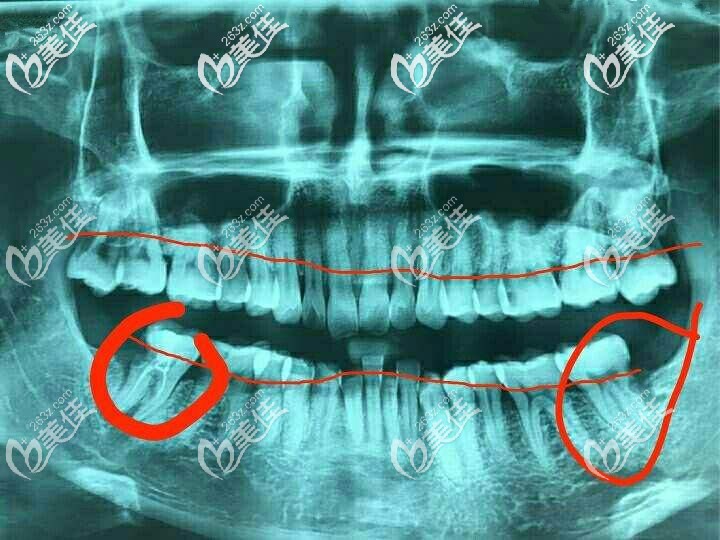

你的牙齒是因為牙周病導(dǎo)致的牙槽骨吸收吧,看你的牙片,牙槽骨吸收的比較厲害,達(dá)到牙根1/3了,是需要先進(jìn)行拔牙治療的。

拔牙之后得先值骨粉,骨粉一般是按克來收費(fèi)的。像0.5g的骨粉一般在3000元左右。骨粉植入牙槽骨后,要等缺損區(qū)骨質(zhì)恢復(fù)正常形態(tài)和功能后才可以做種植牙。

你的年紀(jì)比較小,如果資金充足,建議選擇臨床時間久的種植體,比如瑞士ITI或者德國BEGO這兩款。要是資金有限,奧齒泰也是個不錯的選擇。

牙槽骨吸收一般都是因為慢性牙周炎引起的,我建議你先做牙周治療,讓牙周炎有所好轉(zhuǎn)后在考慮要不要拔牙種植。